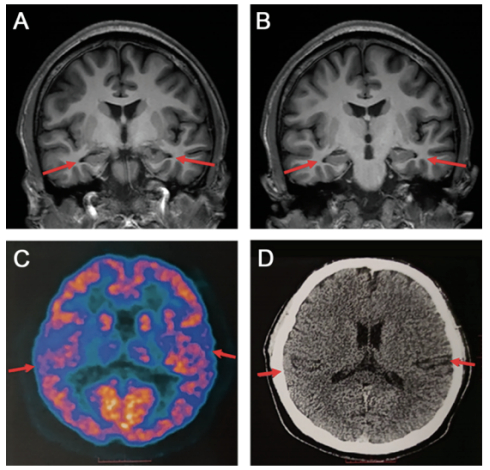

患者脑部磁共振(MRI)结果图

显示双侧海马体(大脑中与记忆有关的部分)已经萎缩⑨

AD大多见于60岁以上的人群,起病隐匿,早期诊断困难,但医学界对于AD最佳干预时间的“黄金窗口期”已有研究。美国国家老龄化研究所和美国阿尔茨海默病协会(NIA-AA)将AD从患者无法察觉的大脑变化发展到引起记忆障碍并最终导致痴呆发生的大脑变化过程定义为“AD连续病程(AD continuum)”③,即在AD患者出现临床症状的10-20年前,AD的病理变化可能已经在大脑中悄然发生④。因此,在疾病早期进行准确识别并及早干预是降低危害的关键。